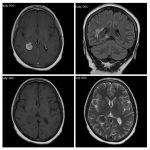

Neurosurgery and neuroradiology always go hand in hand. This little weekly activity is going to enhance the scan reading skills of our audience in an interactive way. Waiting for the answer for a week will keep the curiosity alive and will keep our target audience hooked to the website. It will prove to be a seamless share of knowledge and reading skills.

Dr. Saqib Kamran Bakhshi started the PANS Weekly Image Challenge in 2022, and his creativity and efforts made it a popular activity; engaging trainees and consultants in Pakistan and abroad.